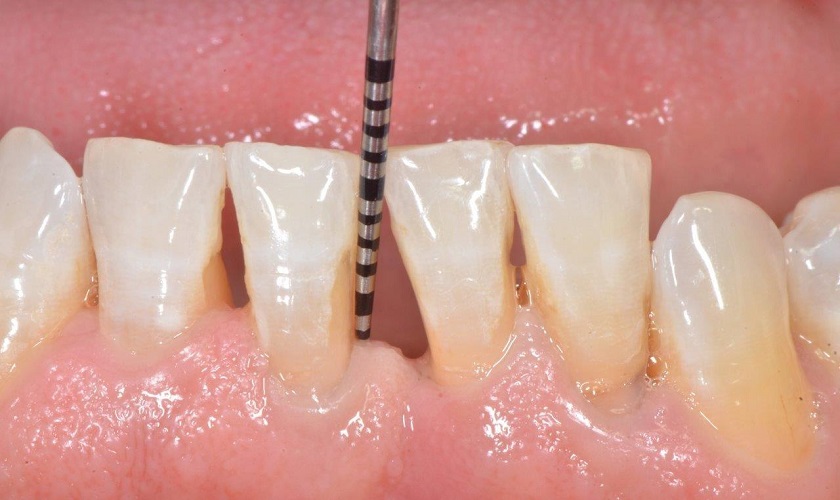

Tụt cổ chân răng(hở cổ răng, hở chân răng, tụt lợi chân răng) là tình trạng các mô lợi xung quanh răng bị mòn. Hoặc mô lợi bị kéo tụt ngược trở lại từ bề mặt răng. Đây là bệnh lý răng miệng khá phổ biến, có thể gặp ở nhiều độ tuổi khác nhau. Trong đó, tỷ lệ bị tụt chân răng nhiều nhất là người ở độ tuổi trung niên.

Những dấu hiệu nhận biết tụt cổ chân răng gồm:

• Hơi thở có mùi hôi khó chịu.

• Răng có cảm giác ê buốt, đau nhức khi ăn uống đồ nóng, lạnh hoặc ngọt, chua.

• Thường xuyên chảy máu chân răng khi vệ sinh răng miệng.

• Xuất hiện các khoảng hở giữa răng và đường viền nướu.

• Nướu sưng đỏ và đau nhức.

• Răng yếu đi và có dấu hiệu lung lay.

• Ngà răng bị lộ ra ngoài, dáng răng trông dài hơn bình thường. Từ đó lực ăn nhai của răng bị giảm mạnh;

• Các kẽ răng bị mắc thức ăn nhiều hơn, gây khó chịu khi ăn uống;

• Bề mặt nướu có thể xuất hiện các ổ viêm, gây đau nhức, mưng mủ.